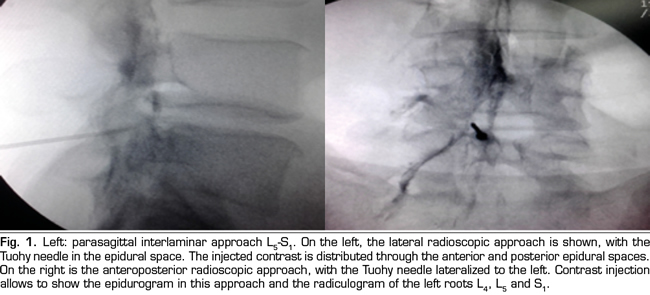

The final position of the needle in the oblique view was the subpedicular zone, while in the lateral view was the anterior superior angle or the roof of the neuroforamen, in the so-called safety triangle (Figure 2). The contrast volume injected was equivalent to the performed in the interlaminar group, obtaining a radiculogram and epidurogram after the injection (Figure 2). The solution of betamethasone was the same used in the interlaminar group, injecting the total volume of the solution in one or two levels, depending on clinical criteria.